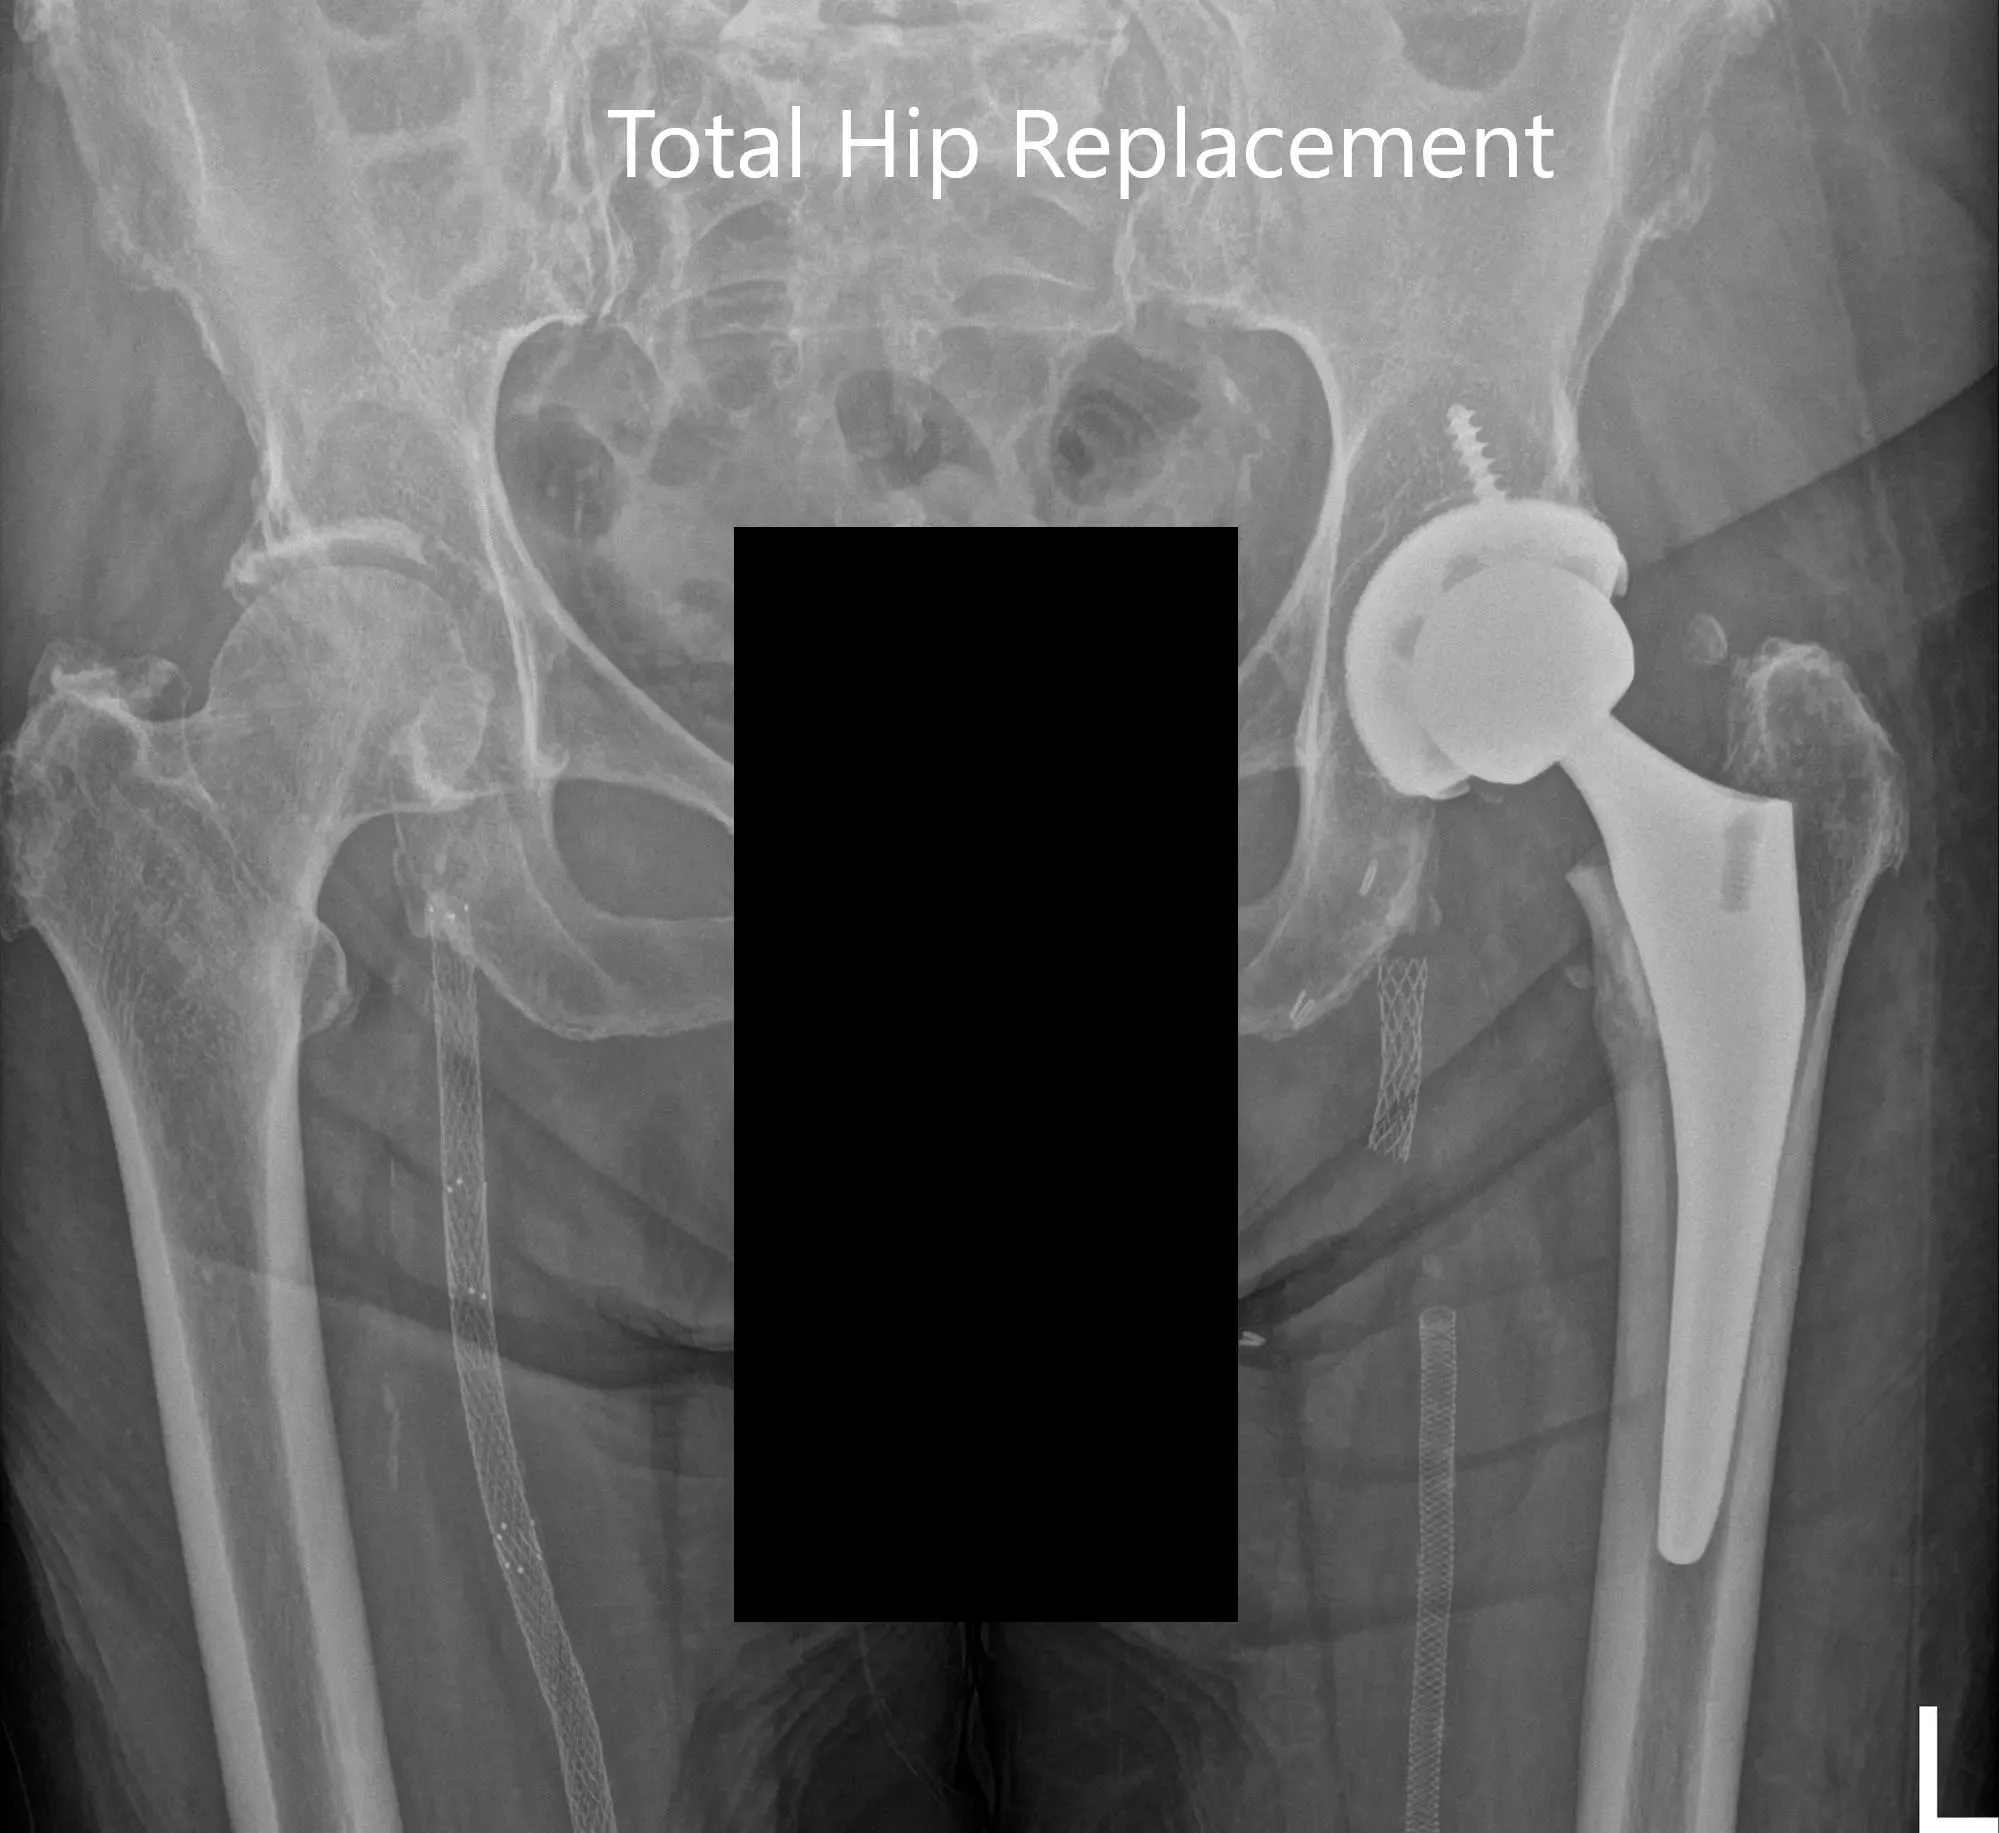

Imágenes de rayos X postoperatorias que muestran imágenes AP y laterales

La recuperación postoperatoria fue excelente, con el dolor bien controlado con medicación. Le empezaron con aspirina 325 mg para la profilaxis de trombosis venosa profunda. Se permitía la carga de peso tolerada con soporte. Las grapas de la herida quirúrgica del paciente fueron retiradas sin incidentes. Su fisioterapia se centró en el entrenamiento de la marcha, el fortalecimiento de músculos y ejercicios de rango de movimiento.